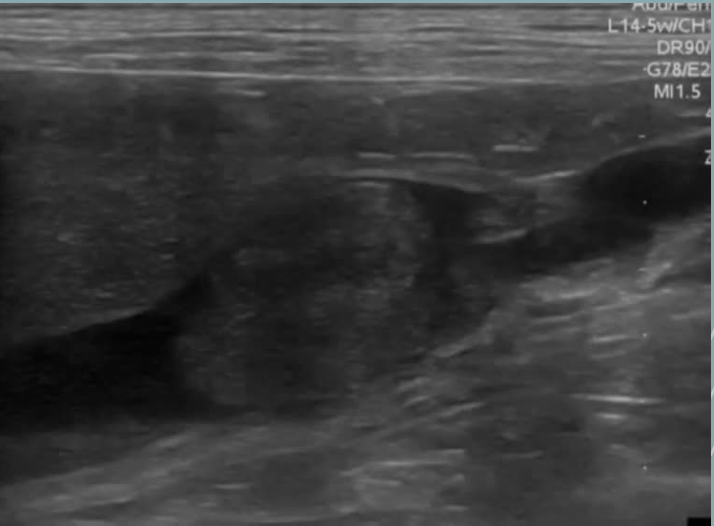

Morfología

Ovalada (haba)

Superficie lisa y regular. cápsula hiperecogénica -

Estructuras

Cortical renal

Médula renal

Septos o columnas renales

Pelvis renal

Hileo renal

vena, arteria y uréter

ECOGENICIDAD

- Bazo > Hígado ≥ Corteza renal